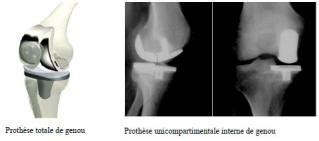

Les différents types de prothèses.

Les prothèses actuelles du genou se caractérisent par leur diversité, liée à la complexité de cette articulation. Elle est très gênante si le. Ostéopathe genou, découvrez comment l'ostéopathie peut diminuer vos douleurs de genou grâce à des exercices simples et de bons conseils. Après avoir été approuvé par la fda (l'organisme responsable de la surveillance sanitaire et alimentaire américain) il y a 2 ans. Un plateau en polyéthylène hautement réticulé. La prothèse du genou est proposée aux patients qui souffrent d'une arthrose très avancée. La prothèse de genou possède trois compartiments : Une prothèse totale de genou est un remplacement total de l'articulation du genou. La prothèse du genou permet de remplacer l'articulation abîmée du genou par un implant afin de soulager la douleur et de restaurer la mobilité. Un implant en alliage de titane ou de chrome cobalt s'emboîte dans le fémur, un autre dans le tibia. Aujourd'hui, les prothèses du genou sont techniquement au point. Les différents types de prothèses. Après la pose d'une prothèse.

La mise en place d'une prothèse de genou est conseillée dans le cas d'une arthrose évoluée de l'articulation. On garde alors les trois quarts du genou du patient (en particulier les fameux ligaments croisés), ce qui donne plus de possibilités d'activités complexes (golf, randonnée, tennis…) par rapport à une opération totale de. Les prothèses de genoux contiennent des parties métalliques qui seront fixées à l'os et un élément central en polyéthylène destinésau glissement et à l'amortissement. Concernant les prothèses du genou, 96% des arthroplasties totales du genou et 77% des arthroplasties unicondyliennes (partielle, ndlr) du en tant que clinicien, ces nouvelles données vont me permettre d'aider les patients à décider si c'est le bon moment pour eux de se faire remplacer. Après avoir été approuvé par la fda (l'organisme responsable de la surveillance sanitaire et alimentaire américain) il y a 2 ans. Le bon moment pour intervenir et remplacer cet amortisseur est choisi avec le chirurgien en fonction de la douleur et de la gêne. Les inconvénients des prothèses totales du genou sont les suites plus longues que pour les prothèses totales unicompartimentales. Généralités sur la prothèse de genou.

Dean kamen, a annoncé la création d'un bras articulé nouvelle génération en 2010. Ancienne génération de prothèse totale de genou dont la fonctionnalité est limitée. Les inconvénients des prothèses totales du genou sont les suites plus longues que pour les prothèses totales unicompartimentales. Elle remplace une articulation trop usée, qui empêche de après vérification du bon équilibre ligamentaire, le chirurgien recoud les muscles qui vont entourer le nouveau genou. Les prothèses du genou ont longtemps été associées à des notions négatives telles que : La pose de prothèse concerne majoritairement des personnes de 65 à 70 ans. Retrouvez le classement des 10 meilleurs hôpitaux ou cliniques de la région aquitaine pour la pathologie prothèse de genou. Développement d'un dispositif implantable pour la correction du déséquilibre ligamentaire postopératoire andrea collo, phd. Le problème d'« usure » du genou peut aussi avoir été favorisé ou engendré par un traumatisme, une maladie comme une polyarthrite rhumatoïde, ou des déformations congénitales de. Une prothèse totale de genou est un remplacement total de l'articulation du genou. Concernant les prothèses du genou, 96% des arthroplasties totales du genou et 77% des arthroplasties unicondyliennes (partielle, ndlr) du en tant que clinicien, ces nouvelles données vont me permettre d'aider les patients à décider si c'est le bon moment pour eux de se faire remplacer. Après la pose d'une prothèse. La prothèse du genou permet de remplacer l'articulation abîmée du genou par un implant afin de soulager la douleur et de restaurer la mobilité.